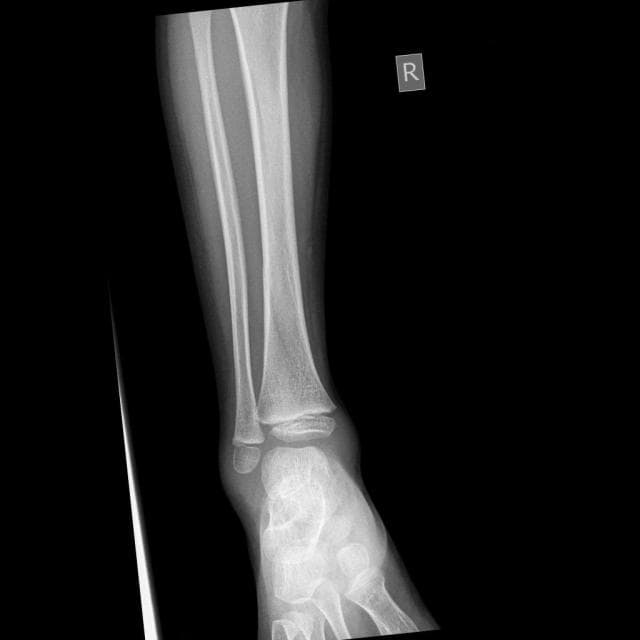

Sample: Oblique Displaced Fracture

Figure 3. Left: Raw X-ray of an Oblique Displaced fracture. Right: HyperColumn-CBAM DenseNet-169 Grad-CAM activation map highlighting the fracture region and surrounding cortical context.